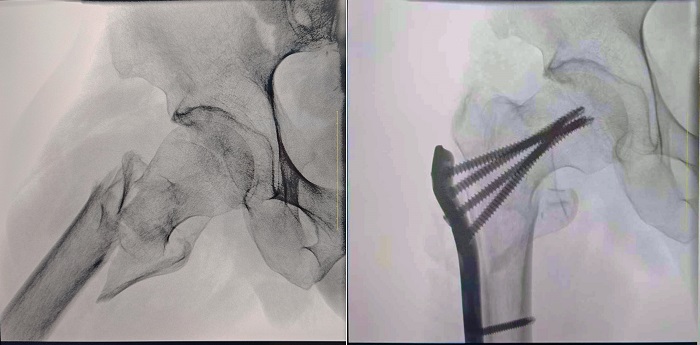

患者:70歲,男

臨床診斷:右股骨粗隆間骨折,伴有下肢位移、外旋

術式:右股骨粗隆間骨折切開復位內固定術

一體式移動C型臂拍攝的術前影像

大視野 高清成像 觀察更全面

普愛醫療一體式移動C型臂采用30CM×30CM的平板探測器,能夠幫助醫生全面觀察患者斷端分離錯位情況,確保手術方案的精準制定。